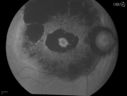

Bullseye Maculopathy without Plaquinel1029 viewsFundus photograph reveals Bull's-eye maculopathy without the use of plaquinel. Patients VA is 20/20, Right eye and 20/25, Left eye. There are reported cases of Scleroderma patients with retinal pigment epithelial atrophy. Will return for follow up in 6-months.      (2 votes)